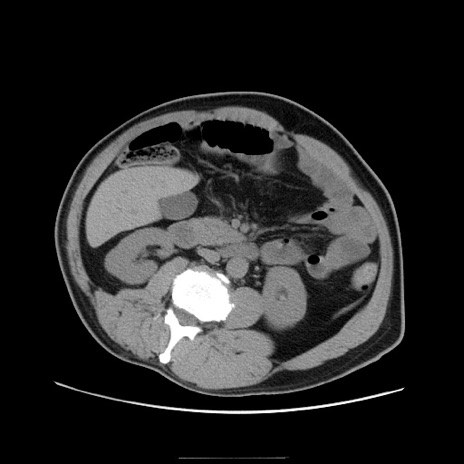

冠状断像

【症例】50歳代男性

【主訴】腹痛

【現病歴】AVMからの被殻出血のため回復期リハ病棟入院中。 本日午後3時頃急に下腹部痛が出現した。

【既往歴】AVM、被殻出血、虫垂炎、高血圧

【身体所見】意識晴明、左半身不全麻痺、会話の理解は良好、36.5°C、腹部:膨隆、全体に板状硬、下腹部正中に圧痛点あり、反跳痛-、筋性防御不明、右下腹部にope scar

【データ】WBC 9400、CRP 0.06